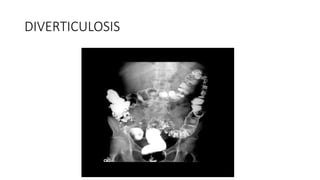

The document discusses the findings from a barium study conducted by Dr. Sandra Johns. It summarizes abnormalities found in the esophagus, stomach, ileocecum, colon, and presence of diverticulosis. Key findings included a dilated esophagus and stomach, thickening and narrowing of the terminal ileum and ileocecal valve, a pulled up and thickened caecum, an apple core sign in the colon, and contrast pooling within diverticula.